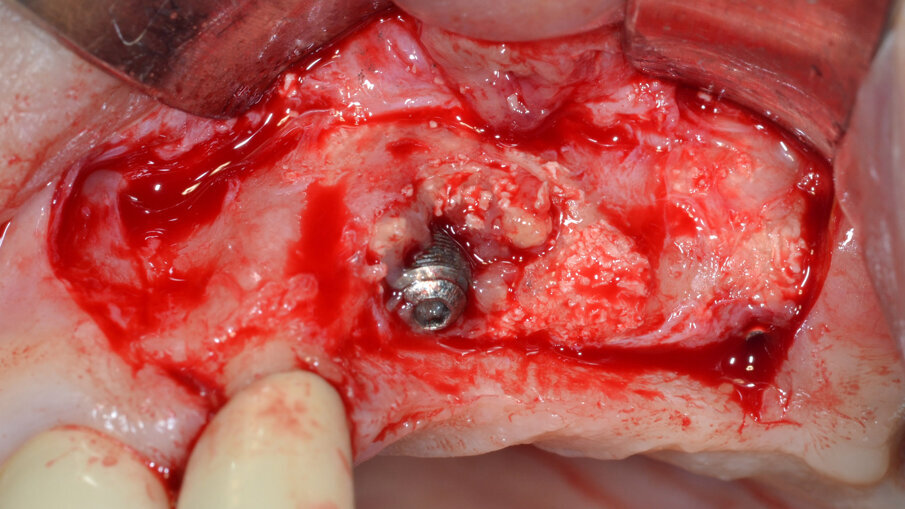

Dopo aver rimosso la protesi fissa e la relativa componentistica, vengono inserite due viti di copertura sterili per consentire una chiusura spontanea dei tessuti molli al fine di poter garantire una chiusura per prima intenzione e una guarigione della ferita chirurgica di tipo sommerso. La procedura chirurgica viene pianificata a distanza di 14 gg. Il primo tempo operatorio consiste nel disegno e nell’elevazione di un lembo di accesso a spessore totale delimitato da un’incisione crestale (effettuata all’ interno della banda di gengiva aderente) e da due incisioni di rilascio verticali leggermente divergenti tra loro (Fig. 3). Al sollevamento del lembo è possibile rilevare un notevole difetto intraosseo peri-implantare; sono inoltre presenti residui di biomateriale non integrato reliquati da un pregresso intervento di rigenerazione ossea (Fig. 4). Il tempo operatorio successivo consiste nel debridement del tessuto di granulazione e dei residui di biomateriale mediante un inserto a ultrasuoni (ES030ACT, Esacrom) (Fig. 5).

Al termine di questa procedura si rimuove la vite di copertura allo scopo di decontaminare anche la superficie interna dell’impianto mediante il dispositivo a cavitazione ultrasonica (PIEZOCLEAN by Dr. Giacomo Tarquini, Esacrom). Il dispositivo a cavitazione ultrasonica “PIEZOCLEAN by Dr. Giacomo Tarquini” è composto da un inserto metallico (da collegarsi a un manipolo a ultrasuoni) dotato di appositi micro-fori per favorire la diffusione del liquido irrigante (ES004E, Esacrom) e da una camera di cavitazione (PIEZOCLEAN by Dr. Giacomo Tarquini, Esacrom) realizzata in silicone di grado medicale appositamente disegnata per consentire un adattamento ottimale alla morfologia dell’osso crestale (Fig. 6).

Fig. 5 - Debridement del tessuto di granulazione e dei residui di biomateriale mediante inserto a ultrasuoni.

Fig. 6 - Dispositivo per cavitazione ultrasonica “PIEZOCLEAN by Dr. Giacomo Tarquini” applicazione del dispositivo “PIEZOCLEAN by Dr. Giacomo Tarquini” e decontaminazione completa dell’impianto.